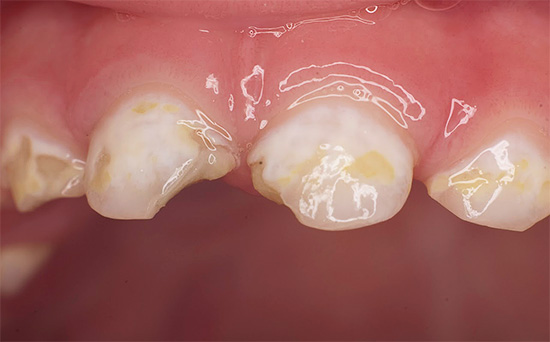

Più avanti nella foto - carie media, che copre più denti contemporaneamente. Una tale lesione simultanea è un segno diagnostico caratteristico della carie in bottiglia:

Di norma, la carie di bottiglia colpisce prima i quattro denti superiori anteriori del bambino. Il processo cariato spesso inizia nella zona gengivale, copre rapidamente l'intero dente attorno alla gengiva lungo il perimetro e penetra negli strati profondi di smalto. Il danno alla zona gengivale del dente è una caratteristica della carie in bottiglia.

In generale, la carie in bottiglia profonda indica un atteggiamento irresponsabile dei genitori nei confronti della salute del bambino: È facile notare la patologia già nelle prime fasi e solo i genitori che possono prestare attenzione ai denti del bambino solo con lamentele costanti possono portare un bambino con denti cariati nella clinica.